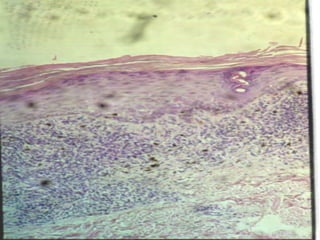

This document discusses benign and malignant diseases of the vulva. It begins by outlining common symptoms of vulvar diseases such as itching, burning, and bleeding. It then provides an overview of the general pathology and terminology used to describe vulvar diseases. The document categorizes vulvar lesions as white, red, or brown/bluish and discusses specific conditions that present with each color, including vitiligo, lichen sclerosis, squamous cell hyperplasia, infections, dermatitis, and various precancers and cancers. Treatment options are provided for some conditions like HPV. Throughout, it emphasizes the importance of inspection, palpation, biopsy prior to treatment, and using medical therapy for benign lesions.